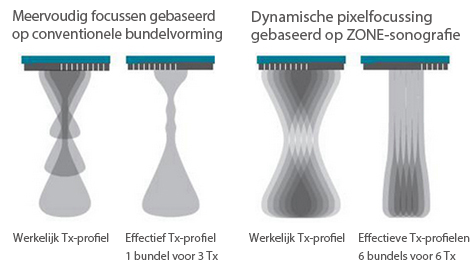

Sinds de oprichting van het bedrijf is Mindray voortdurend op zoek naar nieuwe manieren om het diagnostisch vertrouwen te vergroten. Resona 7 wordt aangestuurd door de meest revolutionaire ZONE Sonography?-technologie. Zijn nieuwe ZST+-tilt de kwaliteit van ultrasoundbeeldvorming naar een hoger niveau door middel van zoneacquisitie en kanaalgegevensverwerking.